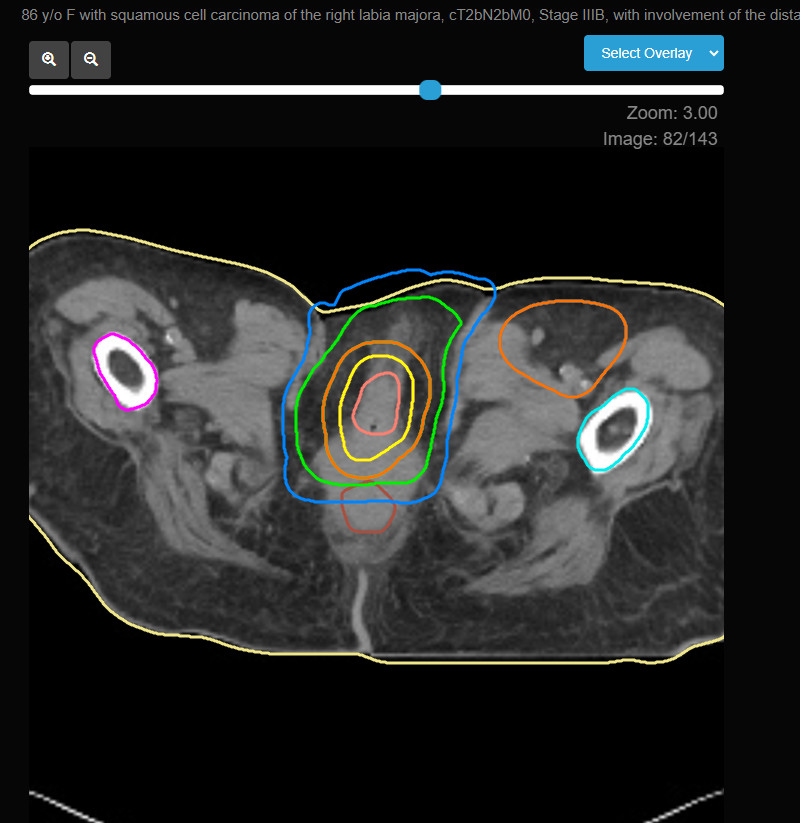

- External Beam Radiation Therapy (EBRT): EBRT is the primary technique used for treating vulvar cancer. Advanced imaging techniques such as CT or MRI are used to precisely define the treatment area, ensuring that the radiation targets the tumor while sparing surrounding healthy tissues as much as possible.

- Intensity-Modulated Radiation Therapy (IMRT): IMRT is often preferred for vulvar cancer because it allows for more precise dose delivery, particularly when treating irregularly shaped tumors or when the lymph nodes are involved. This technique helps reduce the risk of side effects by minimizing radiation exposure to surrounding healthy tissues.